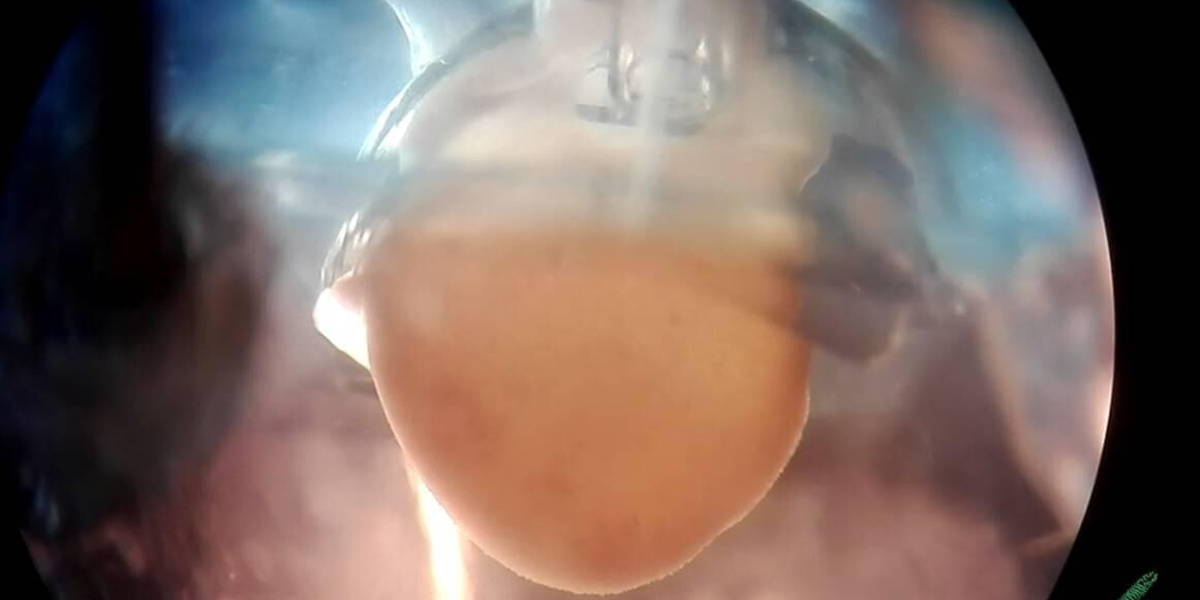

Samen met postdoc onderzoeker Marcelo Ribeiro ontwikkelde Passier een techniek om met de door hem ontwikkelde hartcellen een 3D miniatuurhart te maken dat zelf kan kloppen. In onderstaande video is dat kloppende miniatuurhart te zien.

Het kloppende 3D miniatuurhart